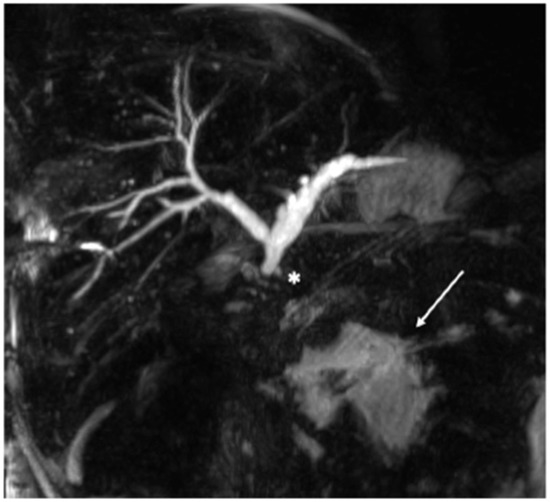

2. Case Presentation